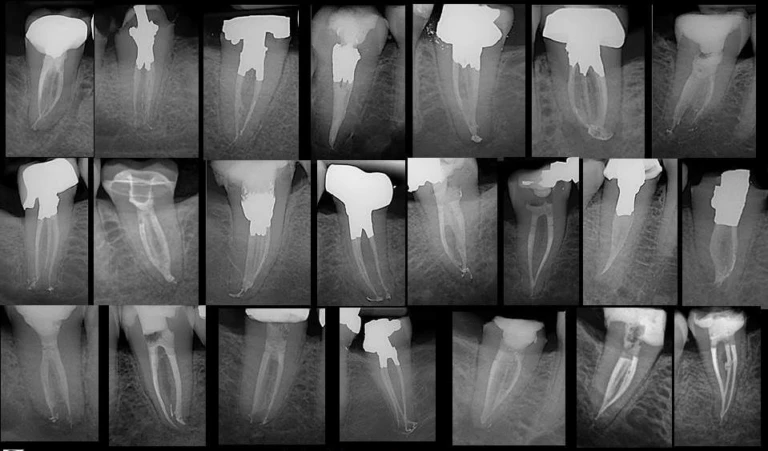

Đọc tiếpPhân tích các hình ảnh X quang của bệnh lý nội nha là một phần không thể thiếu trong chẩn…

Đọc tiếpKhái niệm Các khái niệm truyền thống về giải phẫu chóp răng dựa trên ba mốc giải phẫu và mô…